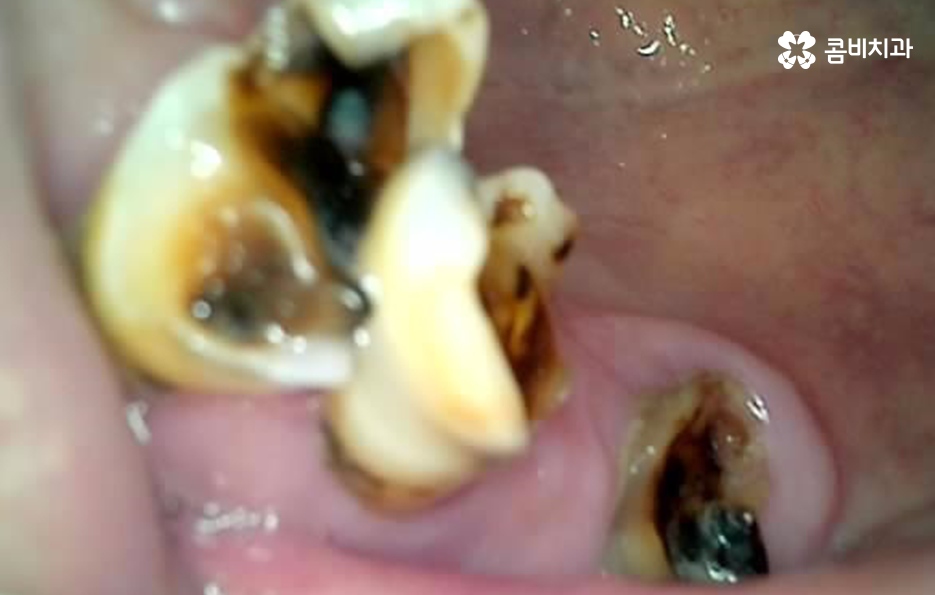

그리고 충치 재발 또는 오래된 보철물의 노후화 문제도 큰데 젊은 시절 충치 치료나 크라운, 브릿지 등을 했더라도 노년이 되면 재 치료가 필요한 경우가 많으며 보철물은 영구적이지 않기 때문에 접착력이 약해지거나 잇몸이 내려가면서 보철물 경계부위에 충치가 다시 생길 수 있고 특히 치아 뿌리 부분에 생기는 충치는 진행 속도가 빨라 치료가 어려운 경우도 많아서 보철물 아래 치아가 불안정해지면 결국 발치해야 하는 상황이 생기는 거예요.